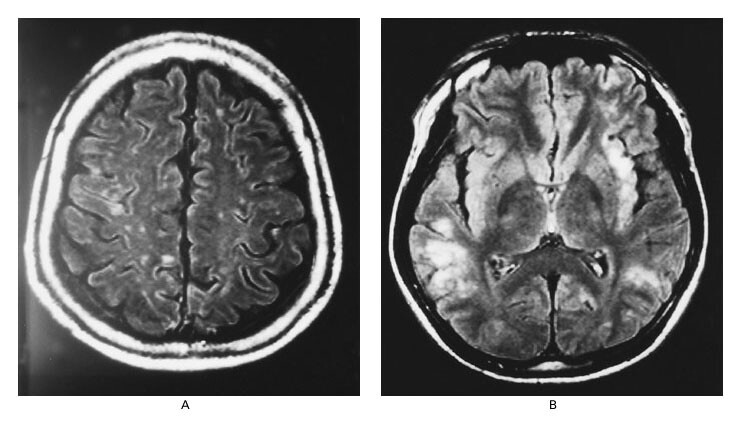

Sau khi xâm nhập vào cơ thể, virus Nipah không chỉ nhân lên tại đường hô hấp mà còn xâm nhập vào các tế bào nội mô mạch máu [3]. Đây là lớp tế bào lót bên trong thành mạch, có nhiệm vụ điều hòa lưu thông máu và bảo vệ các cơ quan. Khi bị virus tấn công, các mạch máu nhỏ, đặc biệt là ở não, sẽ bị viêm lan tỏa. Tình trạng viêm này làm tăng tính thấm thành mạch, khiến dịch thoát ra ngoài mô, từ đó gây phù não [3], [5].

Phù não là một biến chứng cực kỳ nguy hiểm vì não nằm trong hộp sọ kín, không có không gian giãn nở. Khi thể tích não tăng lên do phù, áp lực nội sọ sẽ tăng nhanh, làm chèn ép các trung tâm thần kinh quan trọng. Hậu quả là người bệnh có thể xuất hiện rối loạn ý thức, co giật, liệt, hôn mê, thậm chí ngừng hô hấp và tử vong trong thời gian ngắn nếu không được can thiệp kịp thời [3].

Nói một cách đơn giản, Virus Nipah sau khi vào cơ thể sẽ tấn công mạch máu, nhất là mạch máu ở não. Khi mạch máu bị viêm, dịch sẽ rò rỉ ra ngoài, làm não bị sưng (phù não). Não nằm trong hộp sọ kín nên khi bị sưng sẽ bị ép chặt, làm tăng áp lực trong đầu. Vì vậy người bệnh có thể lơ mơ, co giật, hôn mê, thậm chí tử vong rất nhanh nếu không cấp cứu kịp thời.

Nguồn: American Journal of Roentgenology (AJR) – MR imaging features of Nipah encephalitis.